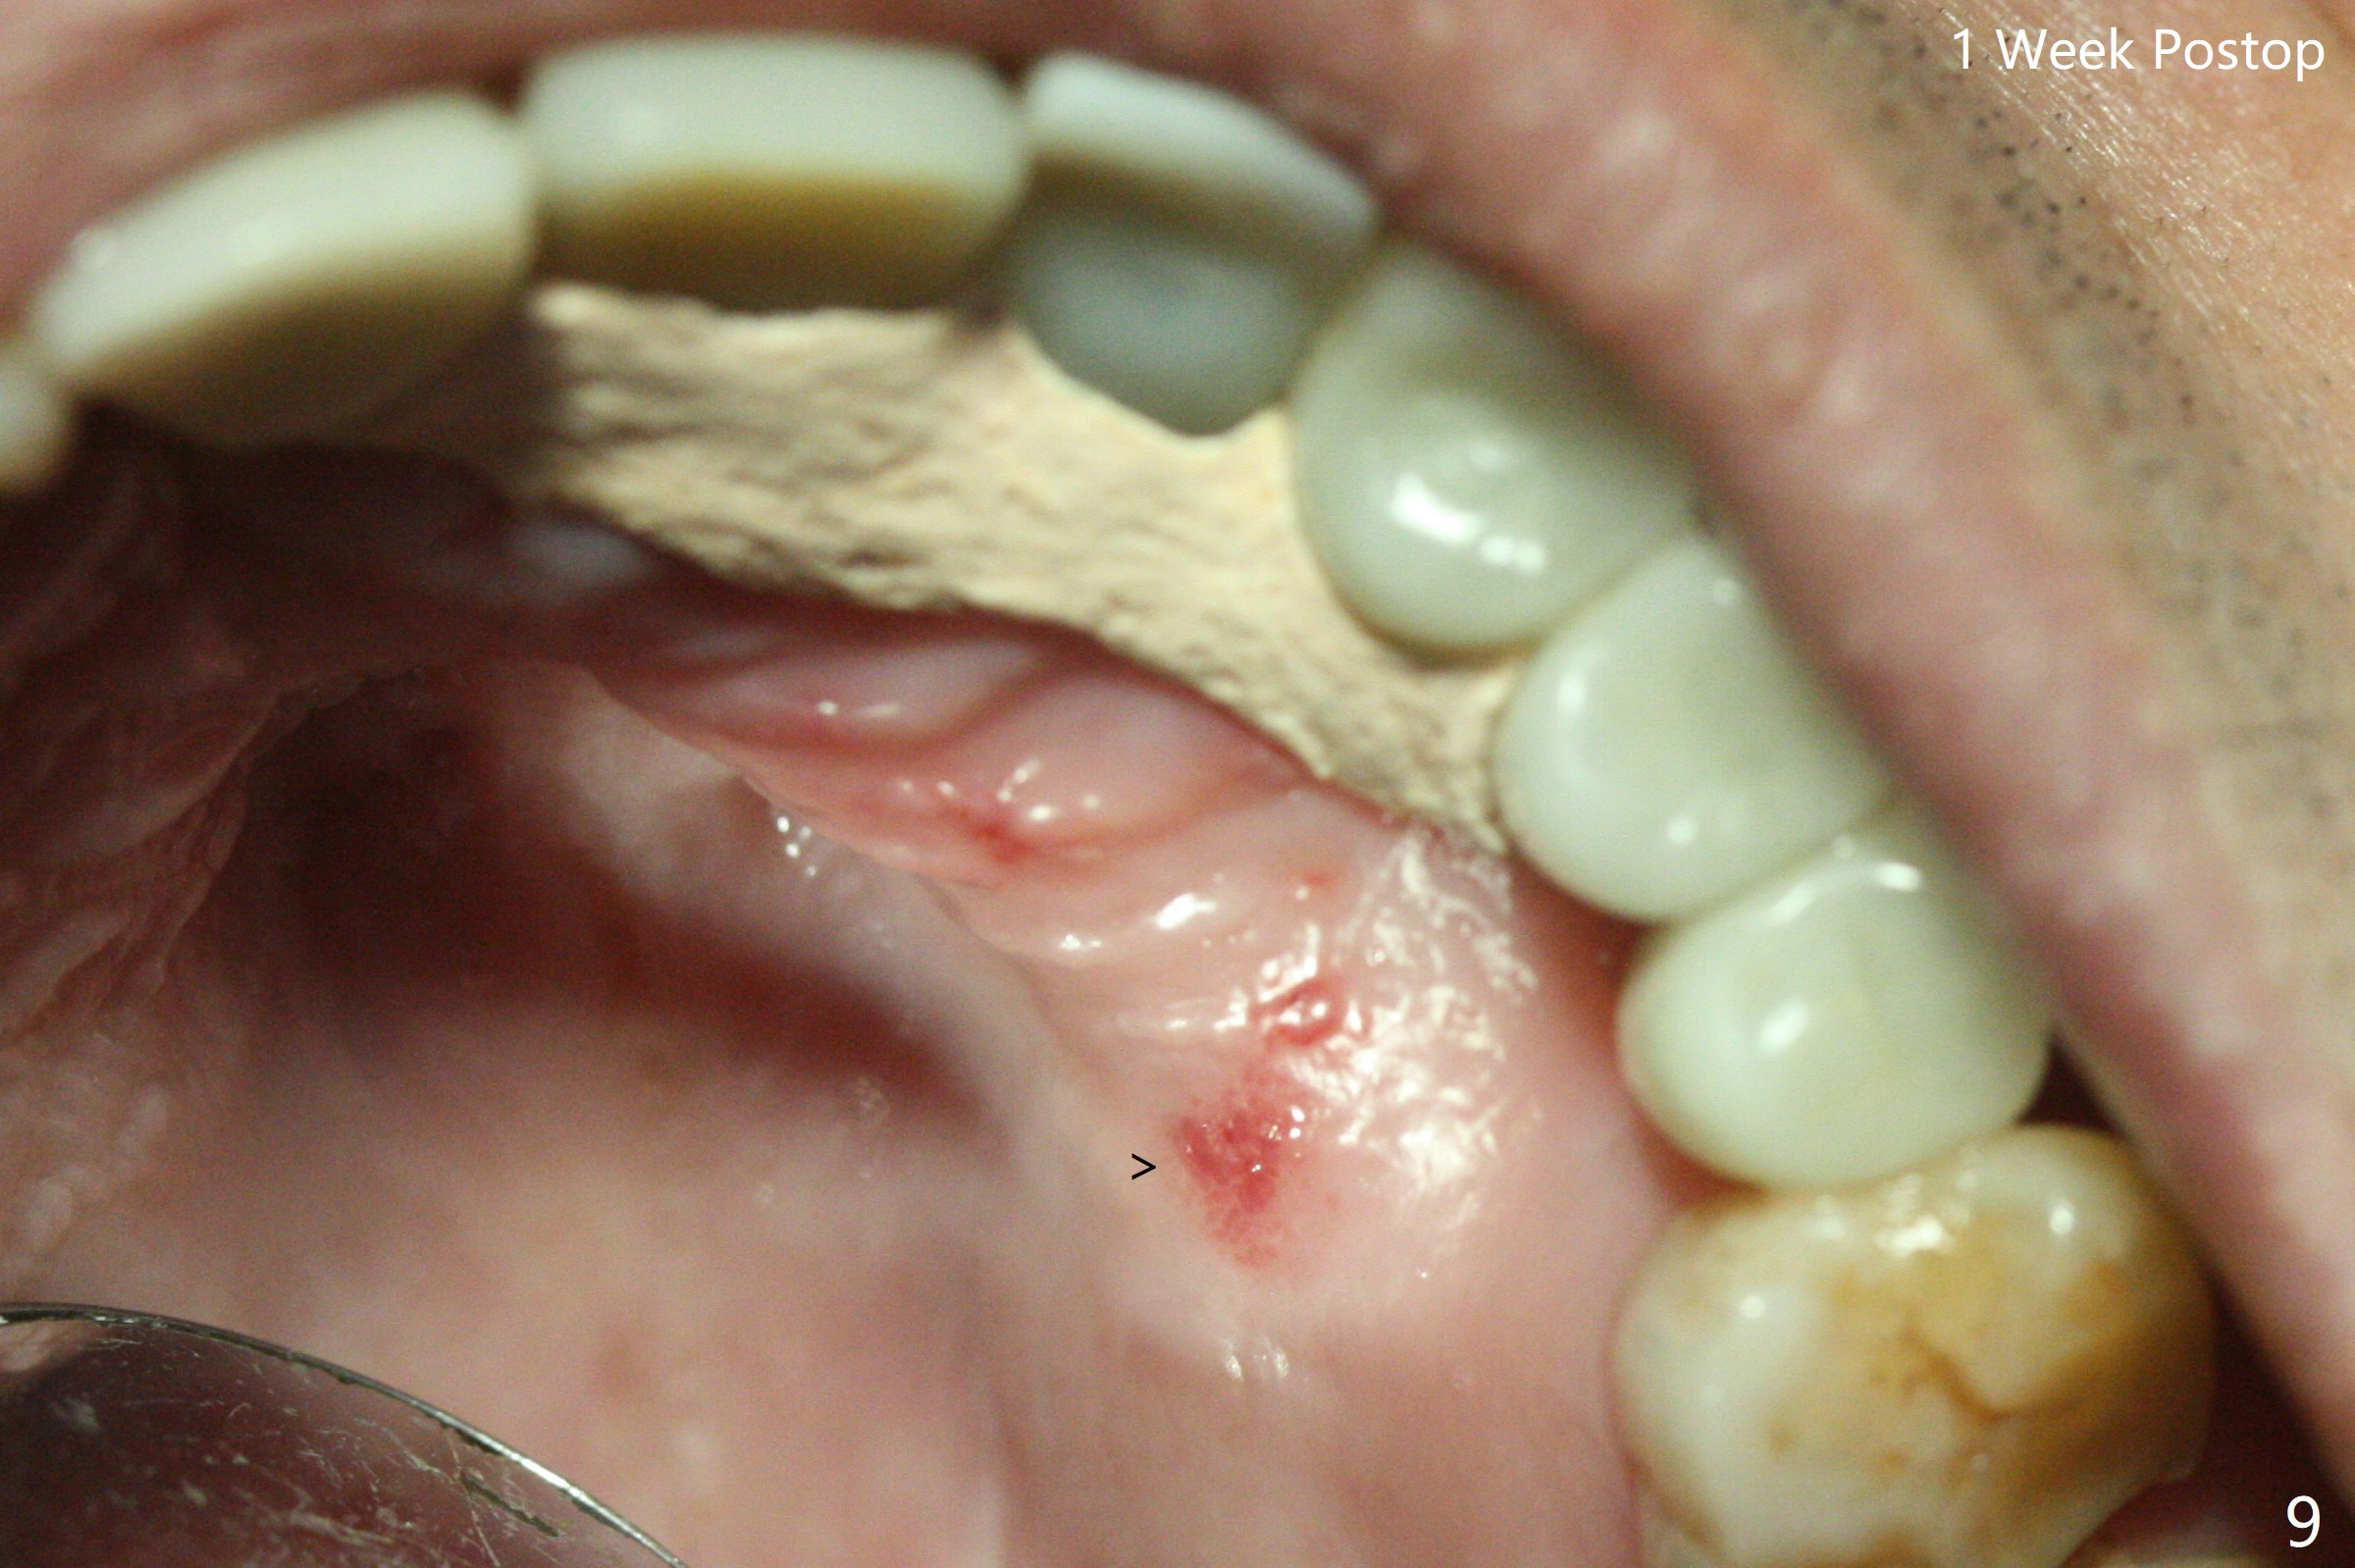

The implant access at #9 closes 1 week post implant fracture (Fig.1,4). There is mild gingival erythema at #10 (Fig.2,3 ^). There is bone around the fractured implant, which is palatally placed (Fig.5). The 2 mm implant is removed using 2/3 mm trephine bur. In spite of moving the osteotomy buccally, a 4.5x4 mm, 15 degree A-type angled abutment is installed for an immediate provisional following placement of a 3.5x10 mm implant (Fig.7, 25 Ncm). Sticky bone is placed (Fig.7 *) palatal to the implants at #9 and 10 (with thread exposure, Fig.6). While the majority of periodontal dressing remains in place (Fig.9,10), the suture in the exposed area appears to hold the papilla in place (Fig.8 <). Herpetic infection develops in the palate (Fig.9). Two months later, the gingiva at #10 is healthy; it appears that the implant threads are covered by bone graft. The immediate provisional (fabricated before suture) keeps the gingiva in an ideal position for impression of final restoration. It appears that the access hole is in a right area for screw retained restoration. The gingival cuff is healthy immediate pre-cementation, 4 months postop (Fig.12,13). The lab does not make access hole for the final crown (Fig.14). The implant remains subcrestal 4 months postop (Fig.15). Since the shade of the crown is off, the abutment remains un-torqued and the crown is cemented with temp bond. The implant threads at #10 seem to be covered by bone graft 4 months postop (Fig.16).